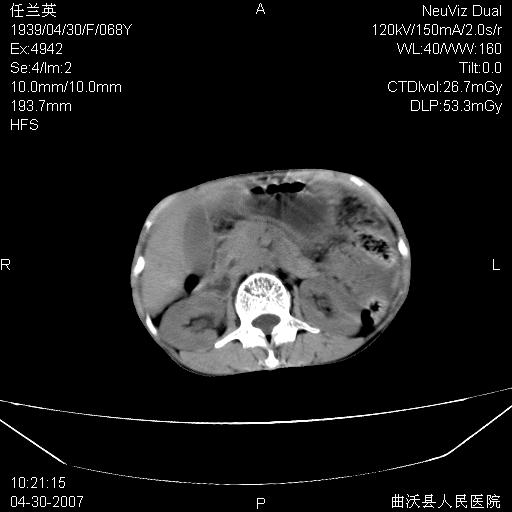

患者,女,68岁,感觉腹部憋涨发硬数天,查b超发现左盆腔有囊性肿物和少量腹水,行ct检查

1.考虑卵巢肿瘤并腹腔广泛性转移可能性大;

2.腹盆腔少量积液。

支持左侧卵巢恶性肿瘤伴网膜、腹膜广泛转移。

难的一见 典型 - 网膜饼  冰冻骨盆 可以当教学片了